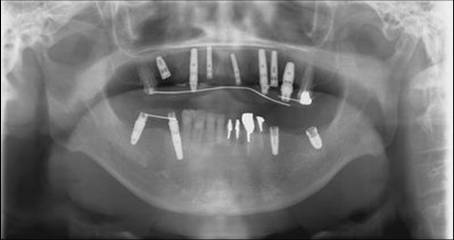

よく我慢されていたと思います。

左上2番の根元あたりがかなりへっこんで吸収されて傷のようになっているのをよく見ていてください。

いずれ歯肉がふくらんできます。この部分には2回弁の手術を行っています。

治療計画

- 上顎8本、下顎4本の設定でいきます。上顎はかなり大きいため、6本よりも8本の方が安全でしょう。

- 右側より始まります。かみあわせの挙上のため、上下一挙に行っていきます。

- 左側も基本的には上下同時埋入。術後、仮歯をつけます。(紹介患者さんですので、右側で噛めるようになれば左下1234の治療を紹介先の先生にしていただきます)

- 最終の仮歯に上顎がかわり、その後最終補綴物ができあがります。

顎はつぶれています。